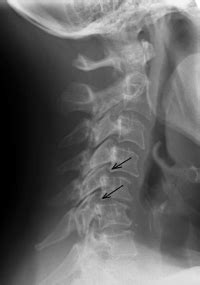

Figuring out if you’ve got cervical facet disease involves a few key steps. First off, your doctor will likely start with a thorough medical history and physical examination . They’ll ask you about your symptoms, when they started, what makes them better or worse, and any past injuries you might have had. They’ll then physically check your neck’s range of motion, look for tenderness, and assess your posture. To get a clearer picture of what’s going on inside, imaging tests are usually the next step. X-rays can show bone spurs, joint narrowing, and other signs of arthritis in the facet joints. However, X-rays primarily show bone, so they might not reveal all the details of soft tissue damage. MRI (Magnetic Resonance Imaging) is often more helpful because it provides detailed images of soft tissues like cartilage, ligaments, and discs. It can show inflammation and degeneration more clearly. Sometimes, doctors might use CT (Computed Tomography) scans , which offer more detailed bone images than X-rays and can be useful for assessing bone structures. A really definitive way to diagnose facet joint pain is through diagnostic facet joint injections . In this procedure, a local anesthetic is injected directly into the suspected facet joint. If your pain is significantly reduced or completely relieved after the injection, it strongly suggests that the facet joint is the source of your problem. This diagnostic step is super important because it helps rule out other potential causes of neck pain and confirms the diagnosis before moving on to treatment.